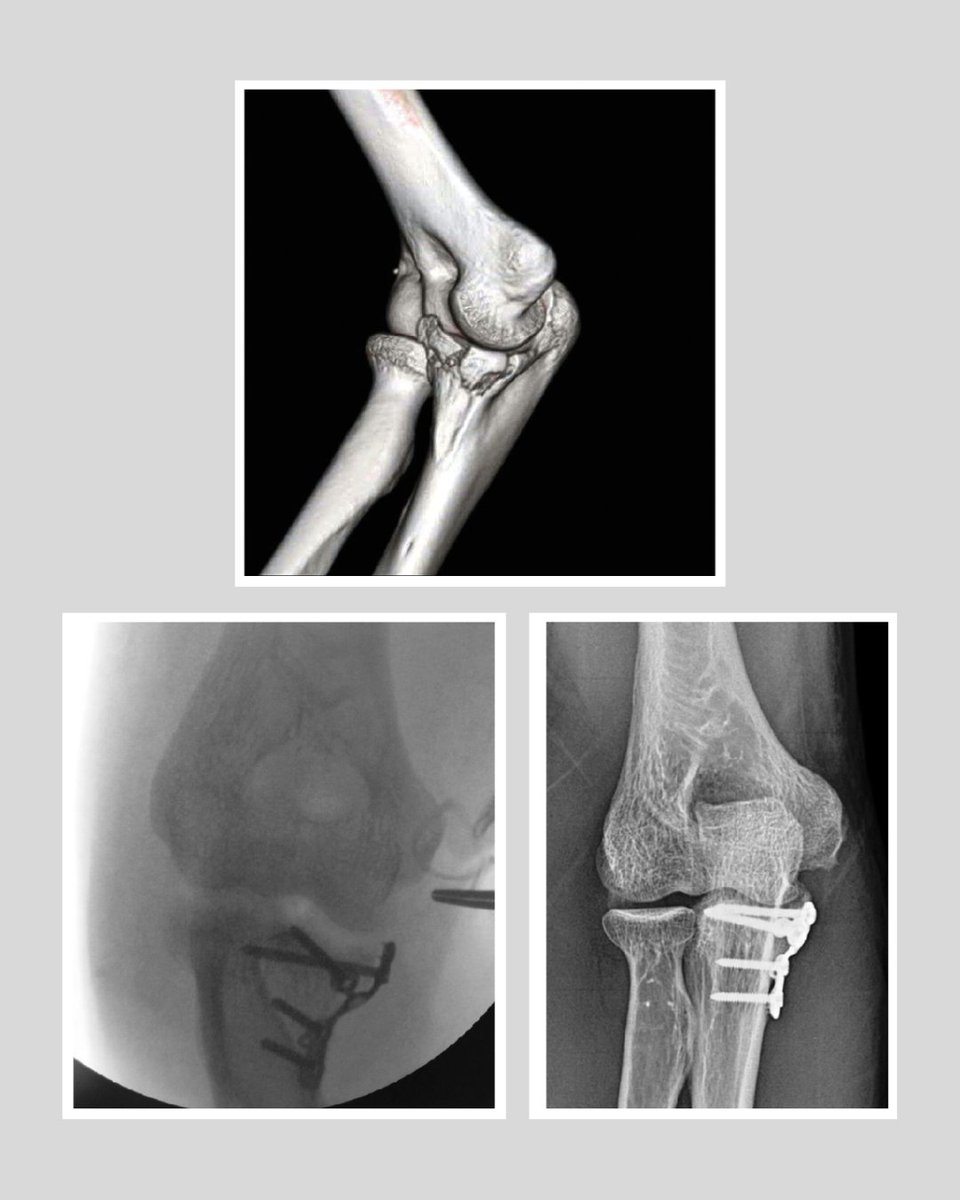

Posteromedial rotatory instability is a rare elbow injury characterized by abnormal rotational instability of the ulna and radius relative to the humerus, often due to disruption of the medial collateral ligament and supporting structures. It is diagnosed through a combination of

Early identification and appropriate surgery are essential in the management of patients with posteromedial rotatory instability of the elbow to prevent the development of early post-traumatic osteoarthritis. #Surgery #Patients #Osteoarthritis #Trauma https://t.co/eOtcqOQ1Le